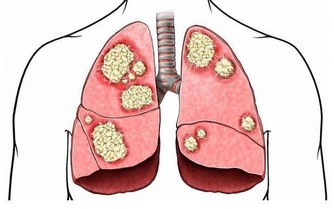

腳氣看似事小,可拖著不治,可能引發手癬、甲癬等,甚至造成丹毒、蜂窩織炎、淋巴管炎等細菌感染。

曾有這樣一例病例:患者是名“老足癬”,一直沒有進行系統治療,後來足部皮膚潰爛,細菌入侵導致蜂窩性組織炎,進而引發全身的膿毒血症,差點沒命!